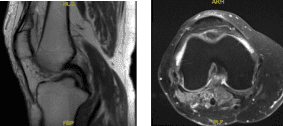

Los resultados de la resonancia mostraron un quiste poplíteo moderado. Subluxación lateral patelina leve. Desgarro del menisco medial, nuevo en comparación con el estudio de resonancia magnética de agosto de 2016. Condromalacia como se detalla a continuación. Los cambios en la señal subcondral, asociados con la condromalacia rotuliana, se han resuelto desde el estudio anterior.

Resonancia – 3T rodilla derecha sin contraste